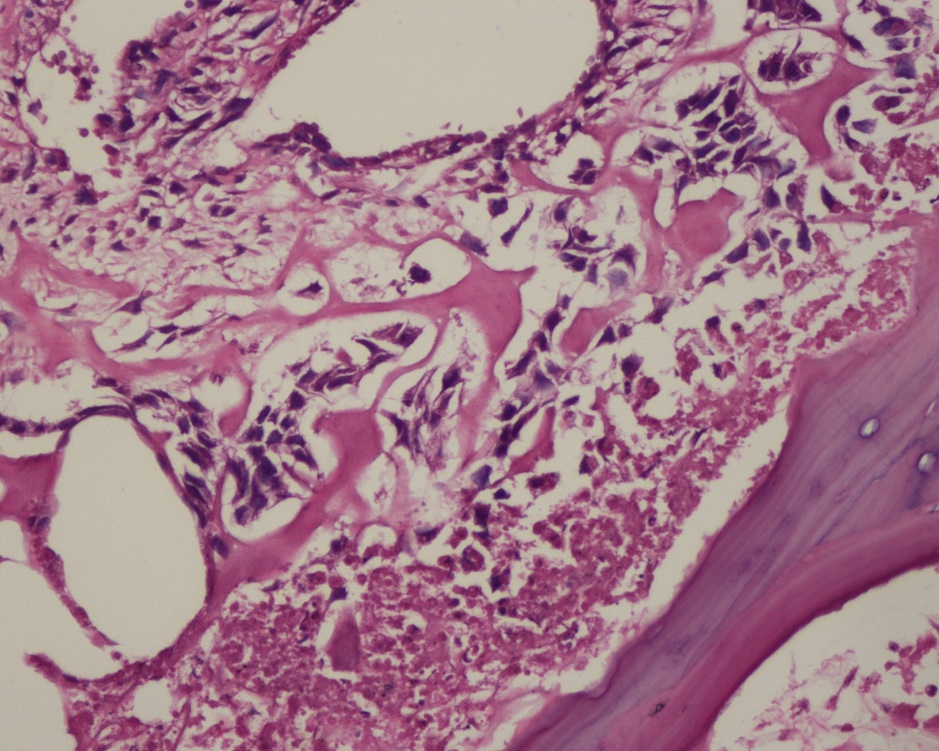

2015年11月27日,术前穿刺(15-33815):(左侧股骨)普通型骨肉瘤。免疫组化结果:CK(-),Vim(+),DES(-),S-100(-),kp-1(±),Ki-67(+约20%)

2016年01月28日,手术病理(16-02811):(左股骨近端)普通型骨肉瘤(成骨细胞型),伴化疗后改变(肿瘤组织内残留大量骨样基质,伴纤维组织增生,局灶区伴出血,部分纤维间质内散在核大、异性肿瘤细胞,未见明显肿瘤细胞的坏死、机化区域约占50%)。